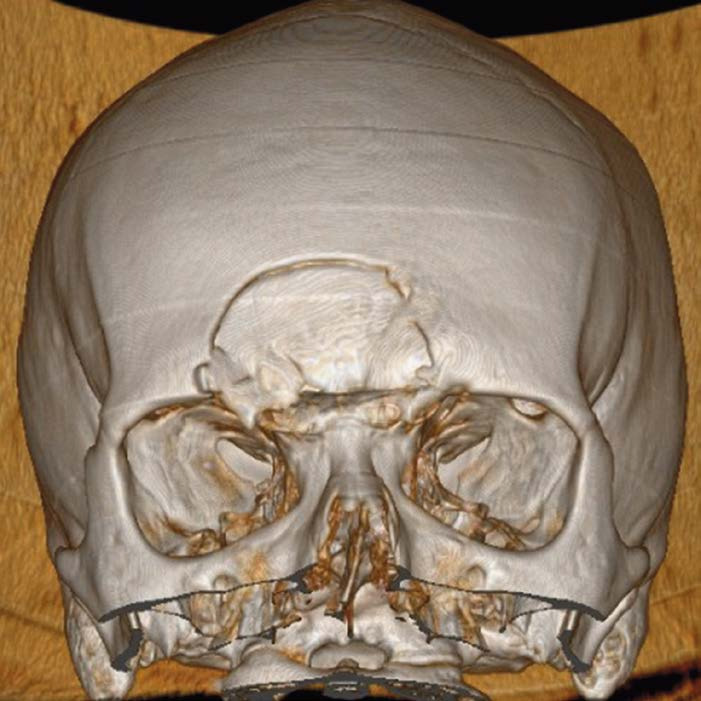

На снимке по МСКТ костей черепа определяется депрессионный вдавленный перелом затылочной кости (обозначено стрелкой)